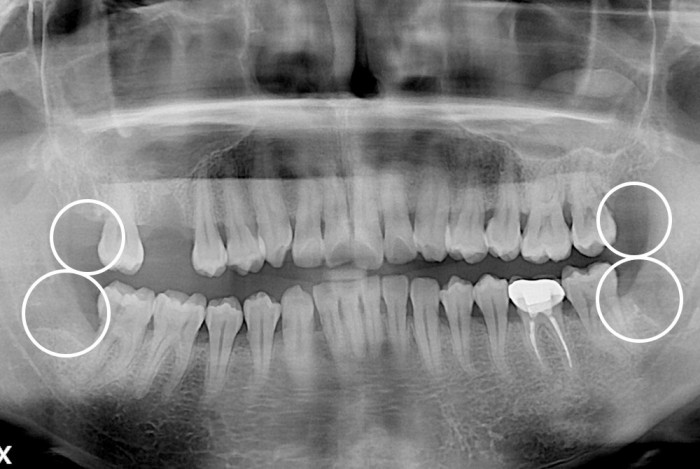

[사랑니] 사랑니

PX20200107_150637_0192_00000000.jpg

치료후 : 2020-01-07

세종치과는 구강악안면외과학 박사이신 원장님이 발치하는 치과입니다.